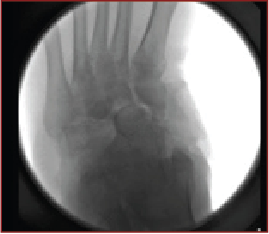

Popularized by Sammarco and colleagues, definitive Charcot reconstruction in a “superconstruct” fashion affirms the need for rigid fixation across the joints and ensuring adequate spanning of the “zone of injury” in order to achieve absolute stability.28 The principle of “beaming” or “intramedullary foot fixation” has continued to gain popularity since its introduction by Grant and coworkers.29 Other authors have since performed this technique with excellent results and osseous union ranging from 73 and 100 percent.28-31 Lamm and colleagues further elucidated technical principles and specific guidelines for accurate screw placement and deformity correction.32

The advantages of intramedullary fixation are numerous as it allows for appropriate spanning of the Charcot segment, incorporates minimally invasive techniques and preserves foot length and anatomic alignment, all through a rigid load sharing system.32 This becomes increasingly important as preservation of periarticular soft tissue supports the neurogenic support to the bone and periosteal blood supply.

Hindfoot stability through fusion has proven successful in Charcot deformity correction with the incorporation of retrograde intramedullary nail fixation. Studies have indicated that intramedullary nail fixation interferes with endosteal blood flow initially but patients subsequently have complete restoration after three weeks in the absence of reaming and complete restoration in six weeks if reaming occurred.33 Typical indications for external fixation are when the patient is not amenable to casting, the deformity cannot have acute correction, evidence or suspicion for osteomyelitis, localized soft tissue infection, or when there is inadequate bone for internal fixation.34

In our experience, a useful indication for external fixation is in the setting of significant concomitant ankle and subtalar joint Charcot in which the calcaneal substrate becomes denuded and is not a stable foundation for intramedullary nail fixation. Many surgeons prefer a combination of intramedullary nail fixation with adjunctive external fixation. Researchers have proven that a combination of internal intramedullary nailing with supplemental external ring fixation has not decreased limb salvage rates.35 The literature seems to support that intramedullary nail fixation leads to higher rates of union but more revision surgery and complications whereas external fixation commonly incurs pin site complications.36,37